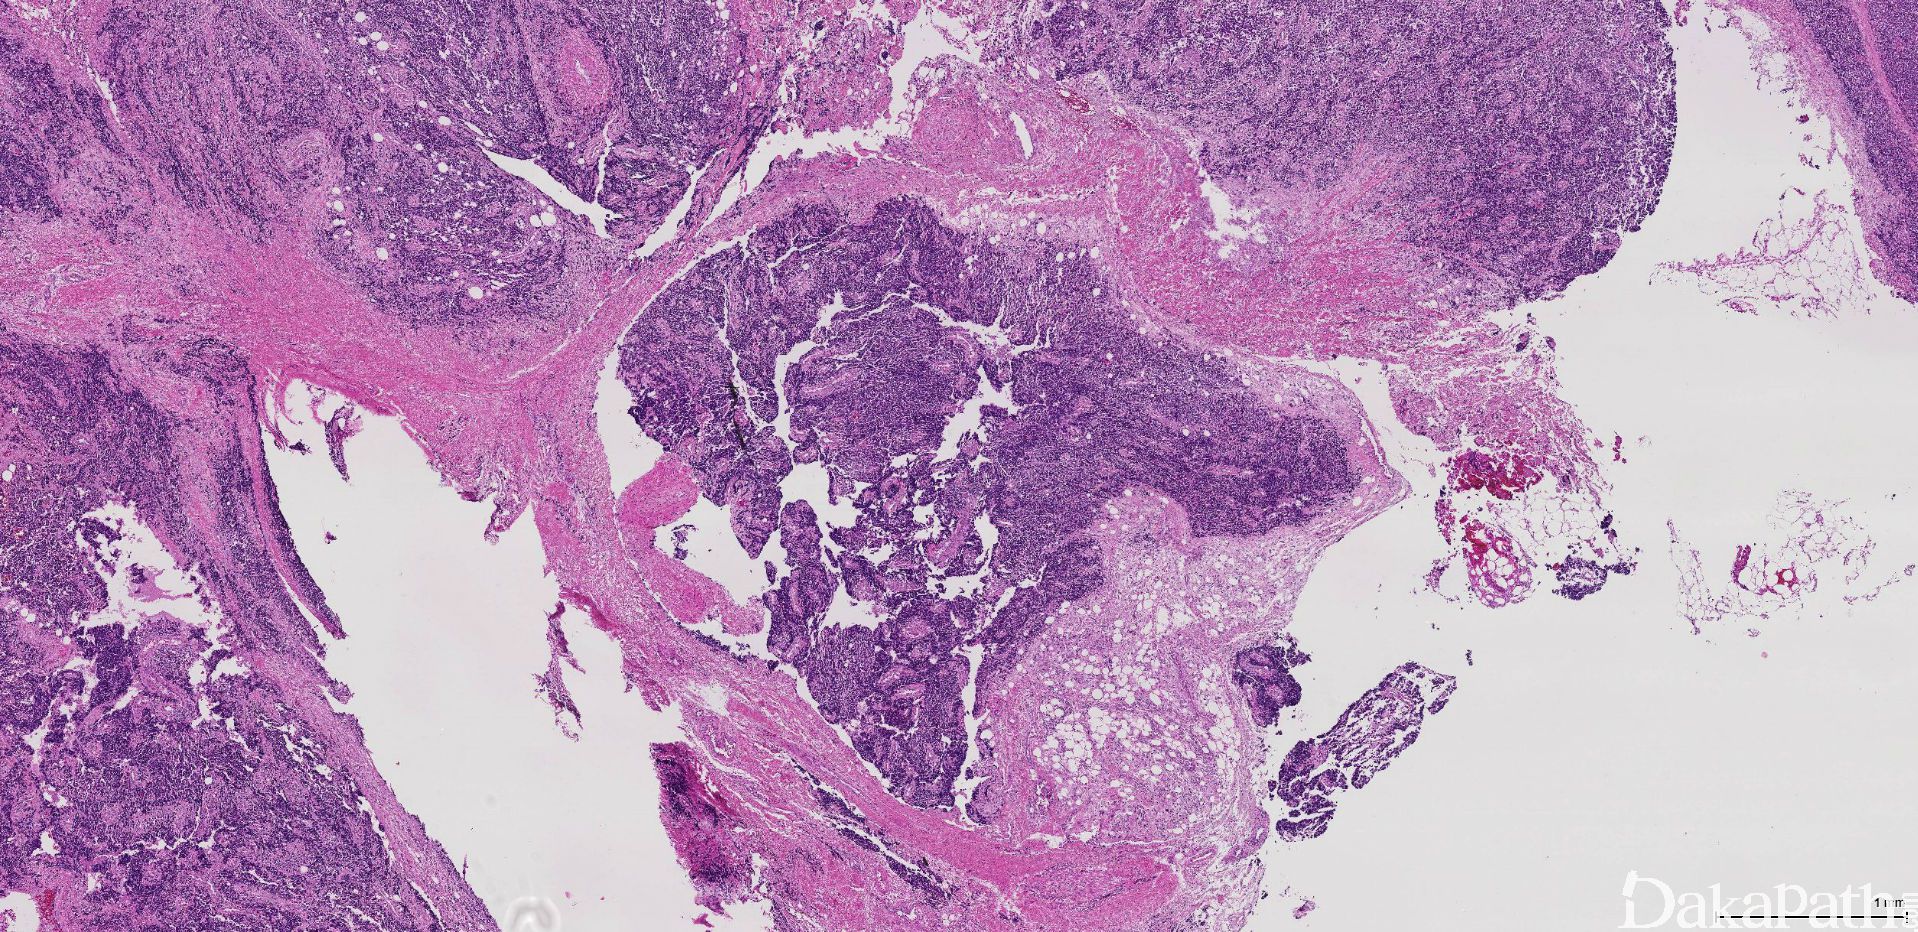

是一种原始小圆细胞恶性肿瘤,组织学上以瘤细胞形成腺泡状结构为特征,并显示有不同程度的骨骼肌分化。

发病部位: 四肢深部软组织,头颈部(包括鼻腔、鼻窦和扁桃体)例,以及躯干(包括脊柱旁)、会阴、盆腔和腹膜后

2. 根据组织形态不同可分为 3 个亚型:经典型、实体型、胚胎性一腺泡状混合型;